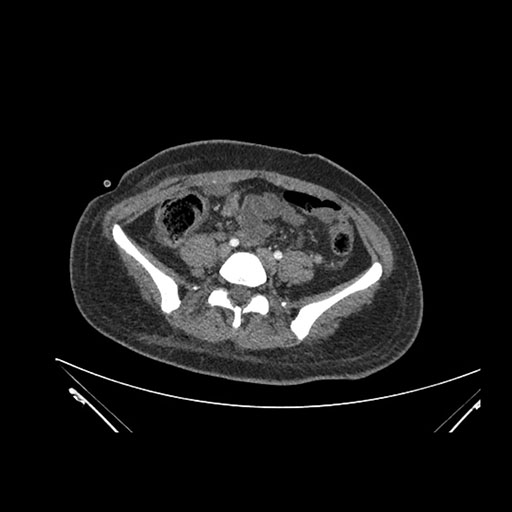

Coronal Venous